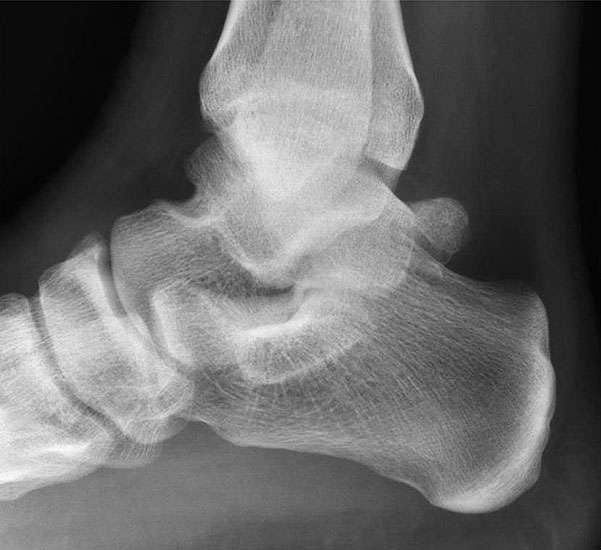

Abbildung Nr. 3 und 4

Die hohen paraachillären Zugänge befinden sich auf Höhe der Außenknöchelspitze unmittelbar medial und lateral der Achillessehne. Zur Identifikation der korrekten Zugangshöhe wird das OSG in Neutralstellung gebracht und eine Linie parallel zur Fußsohle gezogen, welche die Achillessehne kreuzt. Um den N. suralis nicht zu verletzen, wird die Haut nur vorsichtig inzidiert und die Weichteile mit einem Klemmchen aufgespreizt.

Abbildung Nr. 8-10

Es wird zunächst ein Weichteildebridement durchgeführt, bis die Flexor hallucis longus-Sehne identifiziert werden kann. Während des Debridements sollte auf die korrekte Ausrichtung der Instrumentenöffnung nach lateral geachtet werden. Im Verlauf empfiehlt sich der Wechsel auf eine bipolare Ablationselektrode, die eine gezielte Freilegung der Strukturen unter gleichzeitiger Blutstillung ermöglicht, ohne dabei unkontrolliert Gewebe anzusaugen (rechte Seite, m=medial, l=lateral). Das Os trigonum bzw. die Osteophyten sowie die FHL-Sehne müssen vollständig dargestellt werden (*=Os trigonum, FHL=Flexor hallucis longus-Sehne).

Abbildung Nr. 11-13

Das Os trigonum wird aus dem Weichteilgewebe gelöst und anschließend mit einer Fasszange entfernt. Bei größeren Knochenfragmenten muss ggf. das mediale Arthroskopieportal um wenige Millimeter verlängert werden, um die Extraktion zu ermöglichen. Nach Resektion des Os trigonum ist die posteriore Facette des Subtalargelenks erkennbar (rechte Seite, PF=posteriore Facette, FHL=Flexor hallucis longus-Sehne, T = Talus, K = Kalkaneus, *=Os trigonum).

Abbildung Nr. 14-16

Reseziertes Os trigonum sowie prä- und postoperatives seitliches Röntgenbild nach arthroskopischer Entfernung eines Os trigonum.